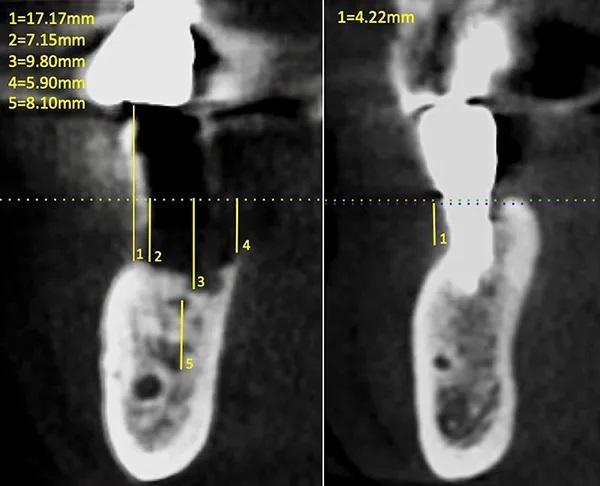

Рентгенологическое исследование области дефекта при помощи прицельных снимков данной области и конусно-лучевой компьютерной томографии (КЛКТ) подтвердило потерю кортикальной пластинки в области щеки от 6 мм до 7 мм, потеря с язычной стороны составила от 5 мм до 6 мм и от 9 мм до 10 мм вертикальной резорбции непосредственно в месте бывшего имплантата 4.5.; также удалось определить, что резорбция началась в области одной стенки альвеолярного отростка (дистальной) и затем процесс распространился (дистально и язычно) образуя дефект. Крыша нижнего альвеолярного канала находилась примерно на 7 мм ниже самой апикальной части дефекта (фото 6).

Фото 6. Измерения размера области дефекта альвеолярного гребня на предоперационной КЛКТ в зоне отторгшегося имплантата (слева) и имплантата зуба 4.4. (справа).

Стандартные рентгенограммы были сделаны сразу после операции и через 8 и 24 недели (фото 10). Вторая КЛКТ была сделана через 24 недели (фото 12). После интерпретации снимка было подтверждено, что благодаря процедуре направленной регенерации костной ткани удалось восполнить достойный обьем костной ткани в вертикальной и горизонтальной плоскости для последующей установки дентального имплантата (фото 6 и фото 12).

Фото 12. Показан снимок КЛКТ через 24 недели после операции с фиксирующими винтами.

После процедуры НРК, установки имплантата и во время последующих заживление тканей прошло без осложнений. Рентгенологическое исследованиеспустя 24 недели после вмешательства (фото 12) потвердило процесс формирования новой костной ткани в вертикальной и горизонтальной плоскостях. В частности наложение изображений первоначального и послеоперационного снимков КЛКТ позволило установить вертикальное и горизонтальное увеличение кости от 7 мм до 9 мм по всей протяженности дефекта (фото 6 и фото 12). Через год после установки имплантата клинические и рентгенологические исследования показали сохранение достигнутой костной регенерации (фото 14).